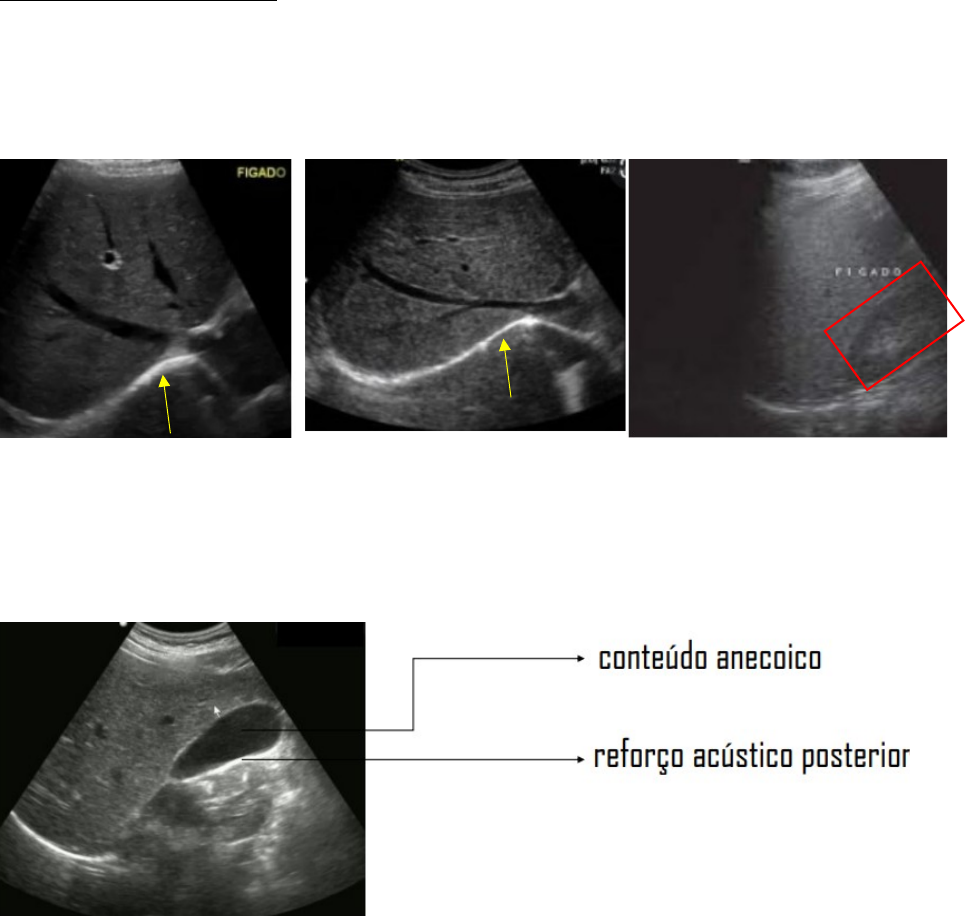

Porção anecoica: estrutura que tem líquido

Apontado pela seta amarela: cápsula de Glisson ou também pode ser uma parte do diafragma

Destacado de vermelho: rim (serve de referencial teórico)

Vesícula biliar: associação direta com o fígado e com conteúdo anecoico dentro

Após estrutura anecoica, existe o reforço posterior (imagem hiperecoica: é um artefato: formação de imagem por característica do método de ultrassom: não necessariamente há uma estrutura mais densa abaixo da vesícula)

Em amarelo: vesícula biliar- hipodensa

Em amarelo: reforço acústico posterior

Cistos: cheio de líquido